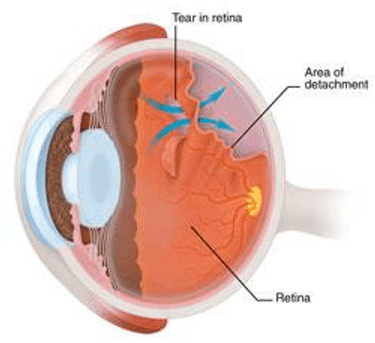

The retina is a sheet of light-sensitive cells responsible for receiving light signals so we can see. The retina is attached to the inner wall of the eye.

The vitreous gel is a gel-like substance that is attached to the retina. Over time, the vitreous gel shrinks and becomes watery.

As the vitreous gel shrinks, it can pull on the retina causing a retinal tear.

What are retinal detachments?

Retinal detachments are when the retina detaches from the inner wall of the eye. This occurs when retinal tears are not sealed early. This results in fluid traveling through the retinal tear and under the retina causing a detachment.